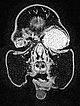

T2-weighted axial MRI with fat saturation. The mass medial to the left eye is relatively homogeneously hyperintense and sharply demarcated from the surrounding tissue. As a sign of strong arterial perfusion, some black, signal-free arterial vessels are seen in the lesion (“flow voids”). This is also typical of an infantile hemangioma.

T2-weighted axial MRI without fat saturation. The mass medial to the left eye is also relatively homogeneously hyperintense in this sequence and shows central flow voids. However, due to the lack of fat saturation, the mass is not as well demarcated from the surrounding adipose tissue.